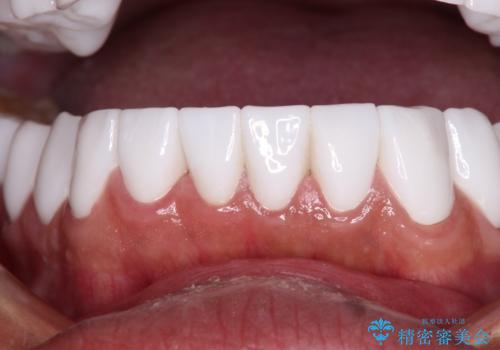

とにかく作り物のような真っ白な歯にしたい フルジルコニアクラウンによる補綴治療

不自然なくらい真っ白にしたいとのことでしたので、透明感のないフルジルコニアクラウンを用いて補綴することとしました。

本来、あまりにも不自然な歯となるため、フルジルコニアクラウンを前歯に使用することは、咬合力が強すぎる場合を除き、ほとんどありません。

それでも、色調、形態ともに不自然なくらい真っ白な歯をご希望でしたので、患者様には大変満足していただきました。